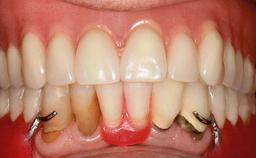

An 83-year-old man presented together with his caregiver at the dental department of the Medical University of Innsbruck, Austria with complaints of swelling in the right maxillary canine area and loss of retention of his 5-years-old mandibular denture. The patient had a significant medical history (20 years) of bipolar affective disorder with moderate depression (F 31.3) and dementia in Alzheimer’s disease (F 00.2). The patient had been in ambulant psychiatric therapy for his depressive illness for the past 20 years. He lived alone and had no children; his sister assisted with daily living. She reported that the patient exhibited compulsive hoarding behavior. In the previous two months, she had noted increasing disorientation and vertigo in the patient. She therefore accompanied him for a medical consultation at the Department of Psychiatry and Psychotherapy of the Medical University of Innsbruck. He was released home after a 6-week inpatient stay.

Patient's Esthetic Expectations Low Medium High

Lip Line No exposure of papillae Exposure of papillae Full exposure of mucosa margin

Esthetic Risk Low